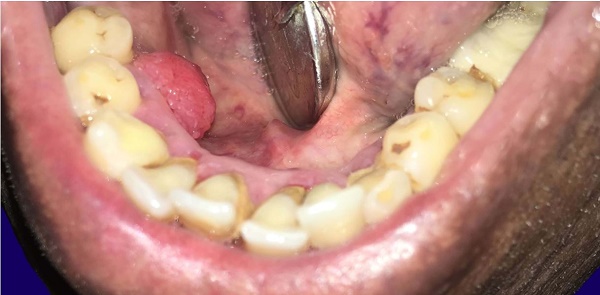

A 72- year old male patient attended the department of oral pathology for evaluation of a painless gingival growth in the premolar region of the right mandible. This lesion has been growing over the last year. The patient referred the excision of a similar lesion 6 years before which was diagnosed as ameloblastoma, but unfortunately, he did not have the previous documentation. His past medical history also included the diagnosis of diabetes mellitus that was on regular control. The examination revealed an oval-shaped exophytic mass of 1×1 cm in the lingual gingiva of the right mandible at the first and second premolar region. The surface was pebbly, with a sessile base and firm on palpation. No local enlarged lymph nodes were identified (Figure 1).